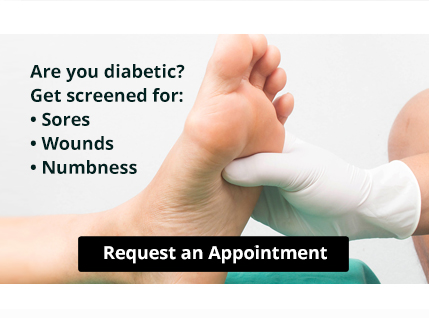

Wounds That Don’t Heal Need to Be Checked

Wounds That Don’t Heal Need to Be CheckedYour feet are covered most of the day. If you’re diabetic, periodic screening is important for good health. Numbness is often a sign of diabetic foot and can mask a sore or wound. The information provided in this...